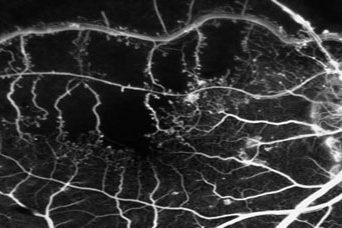

Rétinopathie diabétique Les informations fournies sur ce site sont destinées à améliorer, non à remplacer, la relation directe entre le patient et les professionnels de santé. La rétinopathie diabétique (RD) est une…

Occlusion Veineuse Rétinienne (OVR) Les informations fournies sur ce site sont destinées à améliorer, non à remplacer, la relation directe entre le patient et les professionnels de santé. La rétine reçoit le…